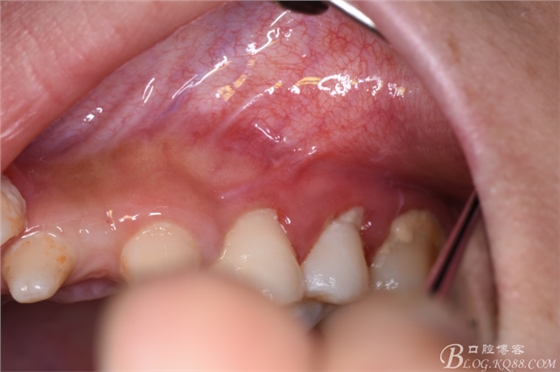

圖5.口內(nèi)觀:22、23區(qū)域的牙齒均為過小牙、牙冠畸形,24根尖區(qū)未能捫及明顯隆起,但cbct的精準(zhǔn)定位,確定切口應(yīng)做在24根尖區(qū)的前庭溝內(nèi)。

圖6.患者的口腔衛(wèi)生不佳,建議潔牙。